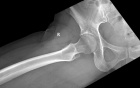

40 year old female presents with c/o burning/stabbing pain in her R anterolateral thigh. Pain has been present intermittently for >15 yrs, but has recently increased in intensity and frequency.

Zoom image: Radiological image Radiological image.